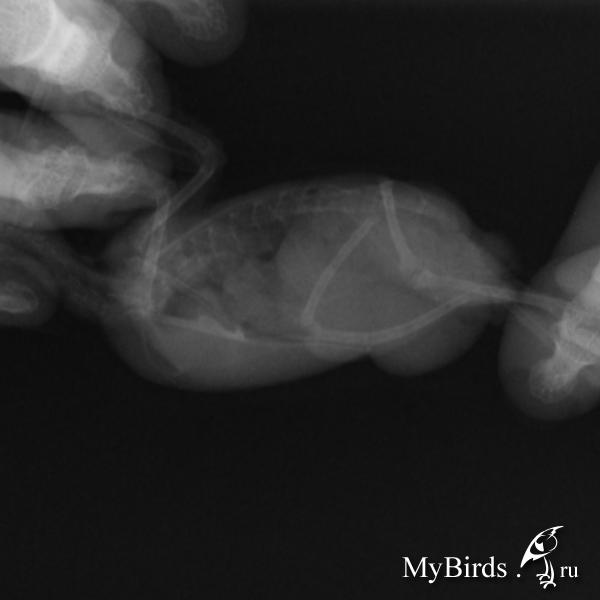

Есть рентген, прилагаю. Очень жду мнения специалиста.

post-42116-1433081614_thumb.jpg

post-42116-1433081628_thumb.jpg

post-42116-1433081652_thumb.jpg

post-42116-1433081673_thumb.jpg

post-42116-1433081688_thumb.jpg

и - срочно - сделать рентген - нужен цифровой, ищите в вет или чел больнице, просите за денги, доза как на хомячка или детскую кисть ребенка, в 2ух проекциях, чтобы разглядеть МЯГКИЕ ткани, снимок выложить на форум- спецы прочтут. (как выложить на форум -см у меня в подписи). Жуть что с животом... ударится не мог? (гематома)

Новообразование вполне может иметь место. тут только пальпация прямая и рентген могут что-то определенное сказать.